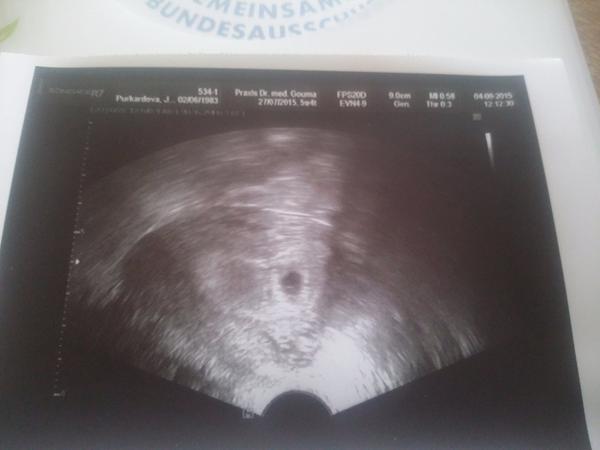

@martinalinda tak to jsem ráda že jste v pořádku dekuji ja doufám že flicek malinko povyrostl aspoň zítra jsem 5+5 🙂